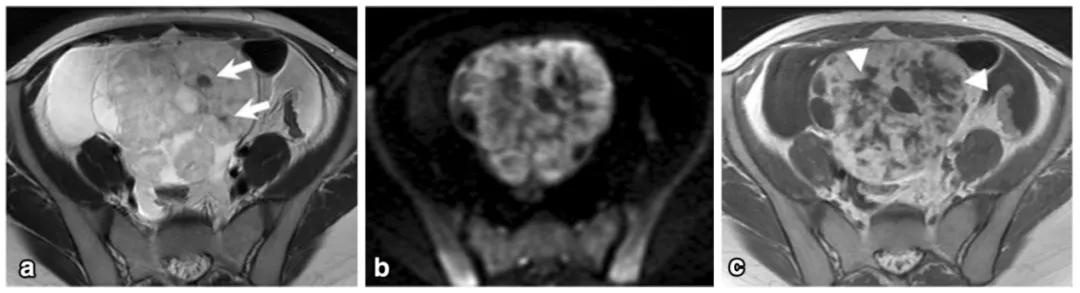

女,61 岁,雌激素升高。MR 显示左卵巢实性肿物,T2WI 呈稍高信号(图 a),内部多发小囊变(白箭),DWI 呈高信号(图 b),增强扫描明显强化。T2WI 显示子宫腺肌症(箭头)。

女,12 岁,卵巢 Burkitt 淋巴瘤。双侧卵巢肿物,T2WI 信号稍高(图 a),DWI 呈高信号(图 b),增强扫描明显强化(图 c),箭头显示肿物边缘多发囊性结节,为卵泡保留征。

女,34 岁,胃癌双侧卵巢转移瘤。T2WI 显示双侧卵巢实性肿瘤,T2WI 呈高低混杂信号(图 a),DWI 呈高信号(图 b)。